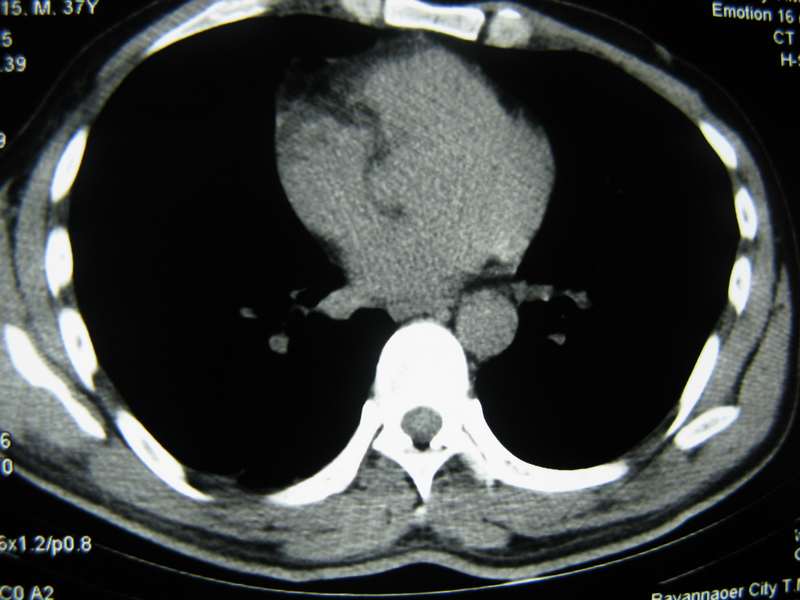

男,37岁,主述胸疼厉害,无咳嗽,无发热,血象也不高,病灶内ct值脂肪密度,右侧胸腔内少量积液,同道们考虑什么?谢谢!

两肺下叶基底段纤维灶,右肺下叶基底背侧相应胸膜肥厚,右肺中叶内侧段部分不张。前中下纵隔团块状脂肪影,随访除外胸腺脂肪瘤。

不除外膈疝。